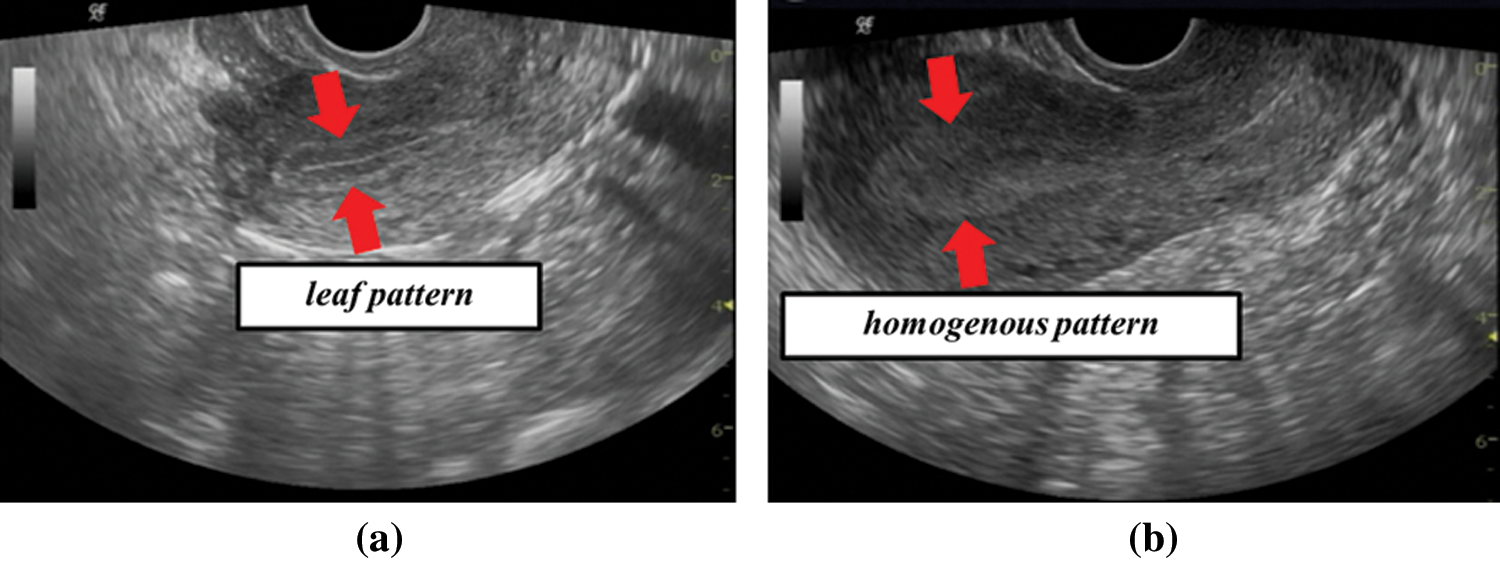

Ultrasonic images of B-mode are often used at infertility treatment. It is known that an endometrial shape displayed on the ultrasonic image is changed with a menstrual cycle [3–5]. Before ovulation, the endometrium has a leaf-like shape as shown in Fig. 1a. This shape is called a leaf pattern. After ovulation, the endometrium has a uniform shape as shown in Fig. 1b. This shape is called a homogenous pattern. A physician evaluates a state for pregnancy based on the endometrial shapes. It is considered that a leaf pattern has a high pregnancy rate and homogenous pattern has a low pregnancy rate. This knowledge is based on relationships between the endometrial shapes and a menstrual cycle. The endometrial shapes in the ultrasonic image are evaluated by physician’s visual observation. However, it is not easy to correctly evaluate the endometrial shapes from the ultrasonic image. In many cases, the treatment fails even if the physician determines a leaf pattern, and the treatment succeeds even if the physician determines a homogenous pattern. In order to correctly evaluate the endometrial shapes, we have proposed an evaluation system for a pregnancy based on a Local Binary Pattern (LBP) feature [6]. A LBP is feature values showing local shape information for an image [7,8]. The proposed system predicts success or failure of a pregnancy from the ultrasonic image based on the endometrium shape information. We confirmed that the system had 70% accuracy. However, it is difficult to improve the accuracy because endometrial shapes displayed on the ultrasonic image are not stable due to the angle of incidence of ultrasonic wave. Furthermore, the proposed method was affected by a uterine direction. In this paper, the authors aligned the uterine direction by rotating images manually. This was subjective. Thus, it is not easy to develop an automated aligning uterine direction method because endometrium has large individual difference for the shapes and sizes. These are serious problems of the proposed system. Therefore, we will develop a prediction system for a pregnancy without LBP from a new viewpoint in order to improve the prediction accuracy.

Figure 1: Examples of ultrasonic images (a) leaf pattern (b) homogenous pattern

It is known that uterus has movements called uterine peristalsis that assists in the transport of sperms, and a direction and frequency of the peristalsis change in each menstrual cycle [9–12]. Uterine peristalsis is mainly observed by using Cine magnetic resonance imaging (Cine MRI) images but it can be possible to observe it by using the ultrasonic images. Therefore, menstrual cycle information can be predicted by analyzing uterine peristalsis from the ultrasonic images. A leaf pattern occurs before ovulation and homogenous pattern occurs after ovulation. A frequency of peristalsis decreases from an ovulation phase to luteal phase. Therefore, it is considered that the movement features at leaf pattern and homogenous pattern are different. A pregnancy can be predicted without depending on the endometrium shapes by analyzing the movement.

The images shown in Figs. 1a and 1b are obtained by inserting an ultrasonic probe into vagina. The image is affected by camera shake because the probe is controlled by physician’s hand. Therefore, it is not easy to extract uterine peristalsis from the ultrasonic images. We showed that movement velocity of uterine peristalsis was 0.68 mm/sec [13]. It is possible to extract only uterine peristalsis from the ultrasonic images by analyzing velocity information.